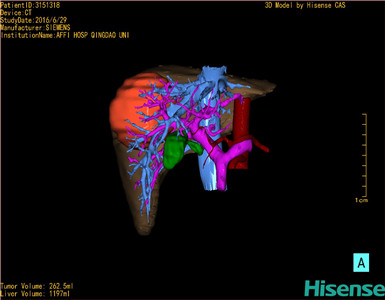

将0.625mm双源薄层CT资料的静脉期和动脉期Dicom格式文件导入海信CAS系统。

通过调节窗宽窗位调整CT序号,对肿瘤,肝实质,胆囊,下腔静脉,肿瘤,肝动脉、门静脉及肝静脉等进行三维重建;系统自动计算肿瘤体积和肝脏体积。

模拟手术操作,自动计算切除肿瘤体积。肝脏体积为1197ml,肿瘤体积为262.5ml,肿瘤体积为肝脏体积的21.9%,通过比对30-40岁正常肝脏体积为1323.35±298.47ml,通过术前模拟手术,精准判断切除后剩余肝脏体积能耐受,避免肝衰竭发生。

术前三维重建:

重建图片